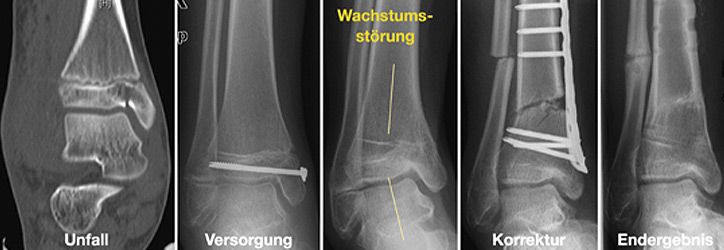

Für die Behandlung von Knochenbrüchen im Kindesalter sind genaue Kenntnisse des Wachstums nötig. Knochenbrüche können das Wachstum hemmen, überschießen oder fehlleiten. Andererseits können Fehlstellungen in bestimmten Grenzen alleine durch Wachstum korrigieren werden. Somit sind für eine Therapieentscheidung die Faktoren Patientenalter, Fehlstellungsausmaß und Korrekturpotenz von größter Bedeutung.

Korrekturoperation

Nur selten treten Wachstumsstörungen oder Verheilungen in Fehlstellung auf. Um dennoch eine volle Belastung und uneingeschränkte Beweglichkeit zu gewährleisten, führen wir entsprechende Korrekturoperationen durch.